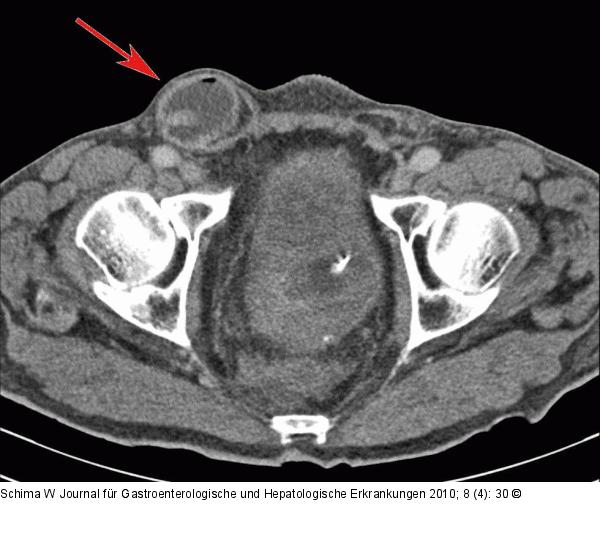

Abbildung 1c: Dünndarmschlinge Man erkennt die Dünndarmschlinge in der Inguinalhernie (Pfeil). |

Man erkennt die Dünndarmschlinge in der Inguinalhernie (Pfeil). |